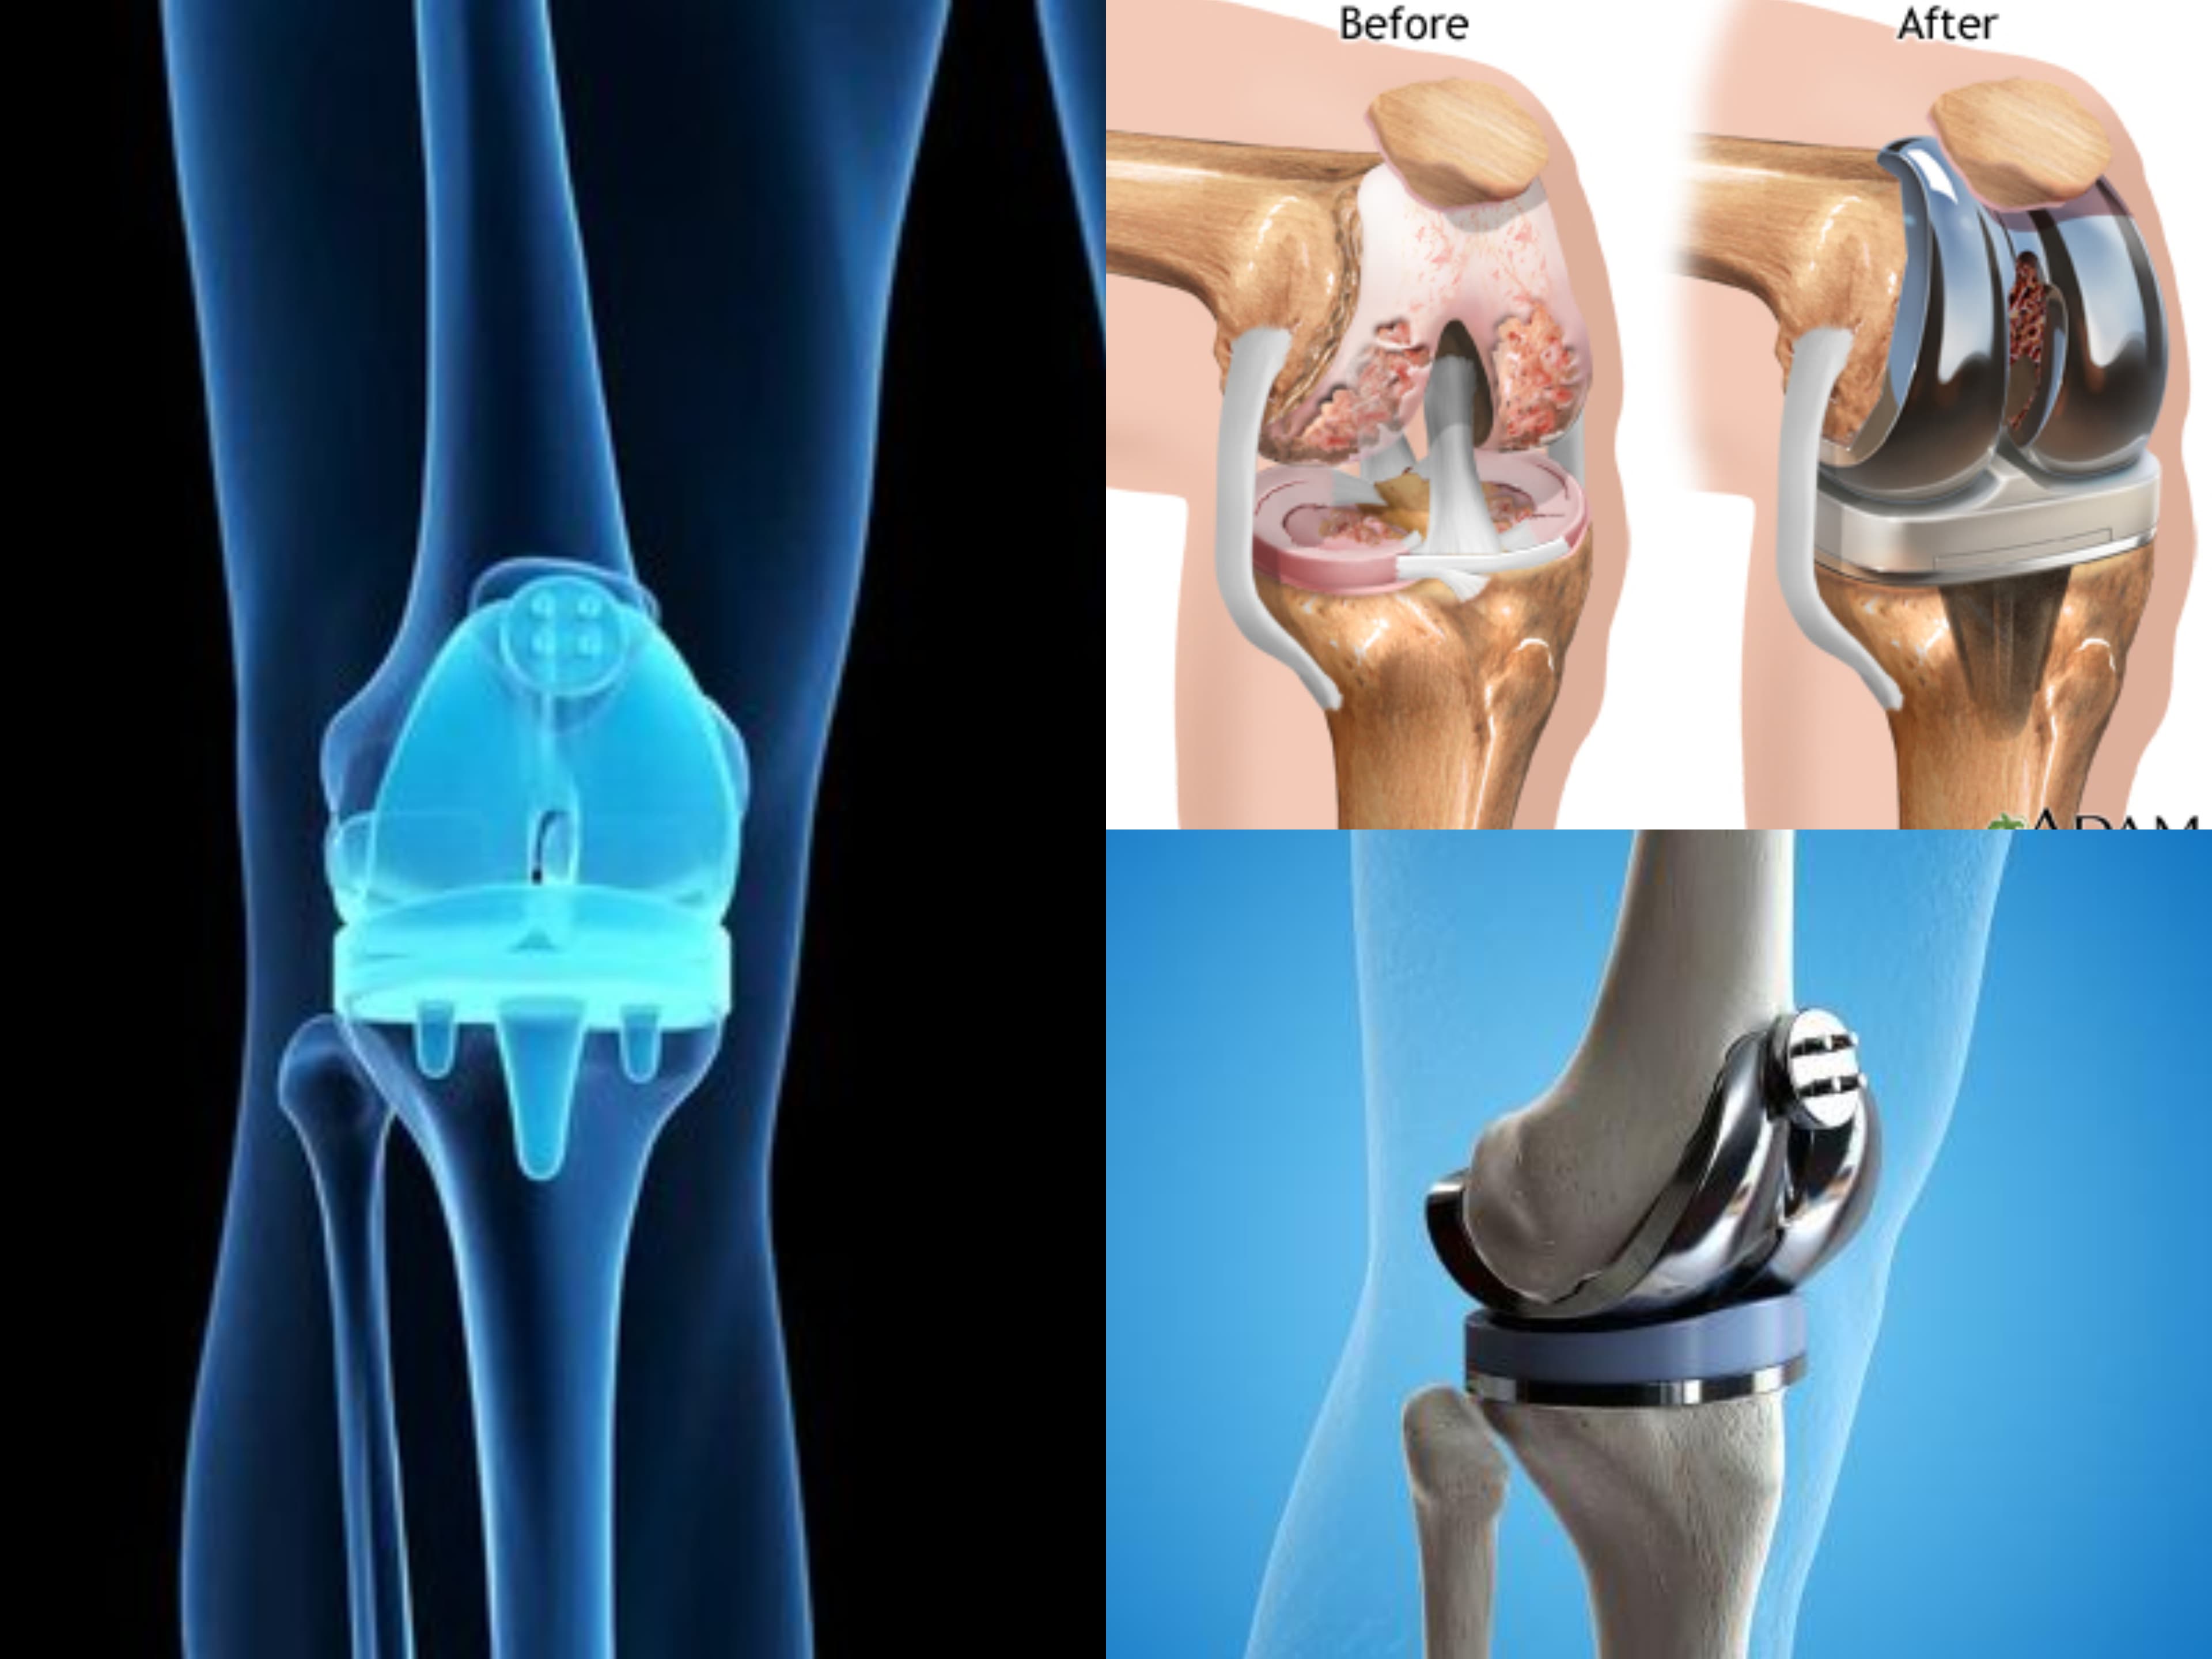

Many users have shared their positive experiences of successful surgeries, such as ACL keyhole surgery, hip replacement, and knee replacement surgeries. The staff is helpful and courteous in assisting patients with formalities and appointments.